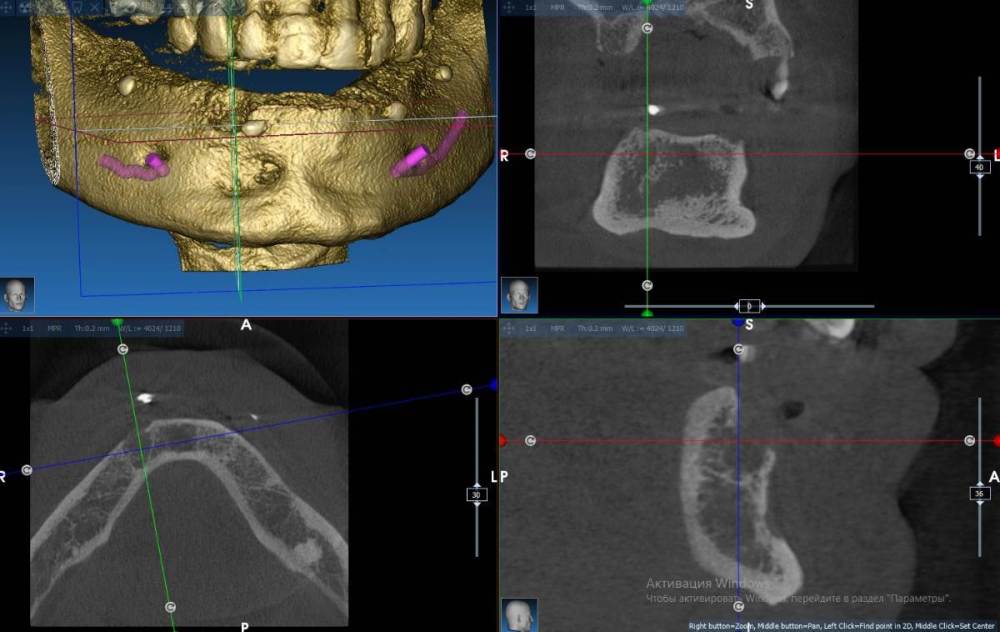

Fin Опубликовано 13 марта, 2022 Поделиться Опубликовано 13 марта, 2022 Здравствуйте коллеги. Появился очень странный вопрос. Год назад у меня был пациент - мужчина 40 лет на консультацию по имплантации все на 6 на НЧ. В процессе осмотра снимка КТ обнаружил в зоне 43 хронический воспалительный процесс. Данный процесс был прокюретажен, пациент отпущен на заживление на пару месяцев. Старый снимок Так получилось что с пациентом мы встретились только сейчас и решили продолжить наше лечение. Далее повторное КТ со скан маркерами на его съемном протезе, сделан слепок протеза- пациент отпущен. В ходе планирования шаблона я обнаружил улучшение со стороны воспалительного процесса но так же обнаружил странное образование рядом не сообщающееся со старым воспалением. Новый снимок Подскажите что это может быть т.к. вижу такое впервые. Сам думаю что скорее всего я преувеличиваю и это из-за того, что снимки сделаны на разных аппаратах, но хотелось бы услашать Ваше мнение. Ссылка на комментарий